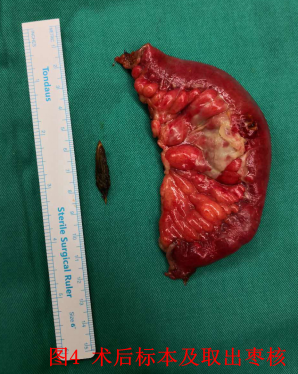

患者:李##,男性,93岁,家住北京昌平天通苑社区,既往患有阿尔兹海默征(俗称“老年痴呆”),无法正常交流。入院前2天出现腹痛、腹胀、恶心、呕吐,自行应用甘油灌肠剂治疗后未见缓解。后出现发热、停止排气排便,就诊于外院,行腹部CT考虑为肠梗阻,给予输液治疗后无效,症状加重,进一步就诊于我院急诊外科,入院时患者神志淡漠,急性痛苦面容,腹部略膨隆,全腹部压痛、反跳痛及肌紧张,患者因不能正常交流,不能描述压痛最重部位。听诊肠鸣音弱。外院腹部CT阅片可见腹腔游离气体,广泛肠道肠壁肿胀,并可见气液平面,考虑为消化道穿孔引起的腹腔感染,并发肠梗阻。血象明显升高(C反应蛋白>200mg/L,白细胞 14.95×10^9/L,中性粒细胞绝对值 12.99×10^9/L,中性粒细胞百分比 87.00%)。因外院腹部CT胶片显示不清,不能明确穿孔部位。急诊复查腹部CT,阅片可见肝周游离气体明确,消化道穿孔诊断明确(见图1。腹腔内肠管肠壁肿胀,可见多发气液平面,考虑为继发性肠梗阻。除外最常见的胃十二场溃疡穿孔及阑尾穿孔。可见左下腹肠道内“枣核”影(见图2,局部肠管肠壁肿胀最明显明显,并可见少量积液。考虑枣核所致小肠穿孔可能大。追问病史家属确认2天前患者进食大枣粥时不慎将枣核吞咽,根据腹部CT提示枣核影位置,反复腹部查体,通过观察患者表情,确认枣核所在部位为压痛最明显部位。综合患者病史、查体及辅助检查结果,考虑患者为肠道异物(枣核)所致小肠穿孔可能性较大。患者如不紧急实施手术治疗,腹腔感染继续加重,会危及老人生命。但患者超高龄,病程较长,全身状况差。心肺脑等重要脏器功能无法完全评估,且患有老年痴呆,围手术期无法配合治疗,围手术期风险极高。充分向患者家属交待手术的必要性及风险后,患者家属表示理解。急诊行手术治疗,术中探查,因患者既往上腹经腹直肌切口下方可见乙状结肠及大网膜粘连,乙状结肠与盲肠、末端回肠及右肝下方粘连,分离粘连,仔细探查腹腔。胃及十二指肠未见明显异常,结肠未见明显病变,距回盲部约160cm处可见小肠局部大量脓苔,肠壁可见异物(枣核)刺穿肠壁(见图34,局部炎症较重,肠壁糜烂,局部腹腔及盆腔可见淡黄色脓液,量约400ml